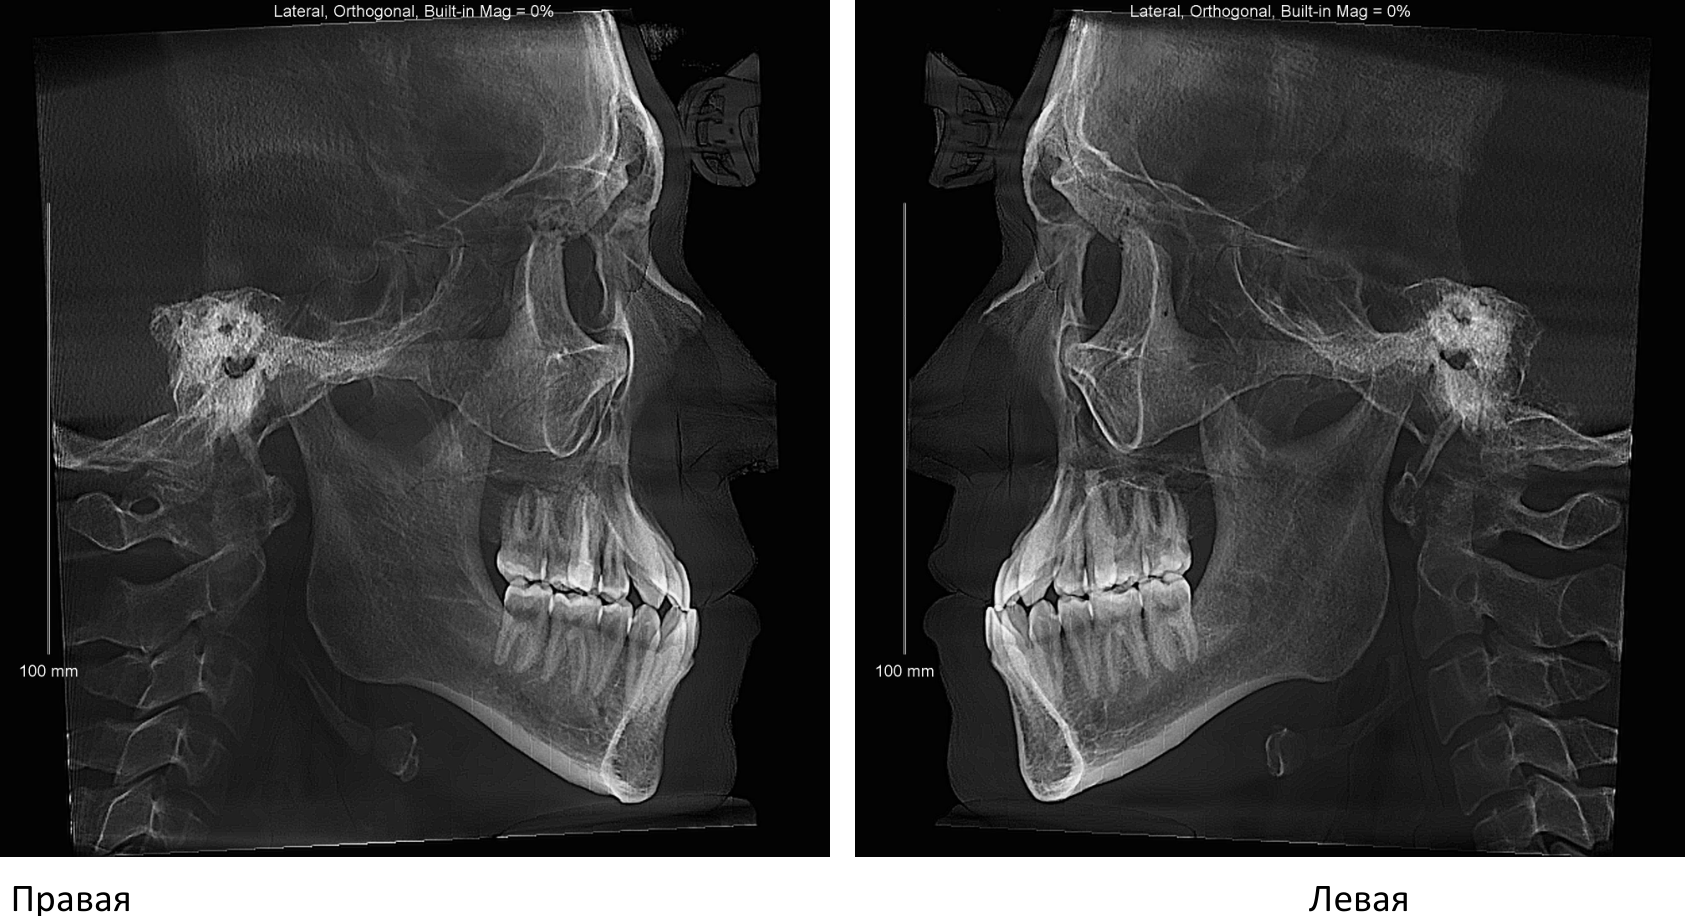

ВНЧС.jpg

23 года, мезиальный прикус, 3 класс

ортодонт сказал пик 1 самое главное, от этого зависит можно ли просто вытянуть зубы брекетами не проебав шейки и дёсна

эту хуйню кто-то умеет расшифровывать?

ну и самое ебаное, на верхней челюсти зубы стоят в 2 ряда

а вот пик 4 - ещё хуже, тут видно, что верхняя челюсть уже нижней на 2мм, что то значит? а это значит, что надо пилить без вариантов!